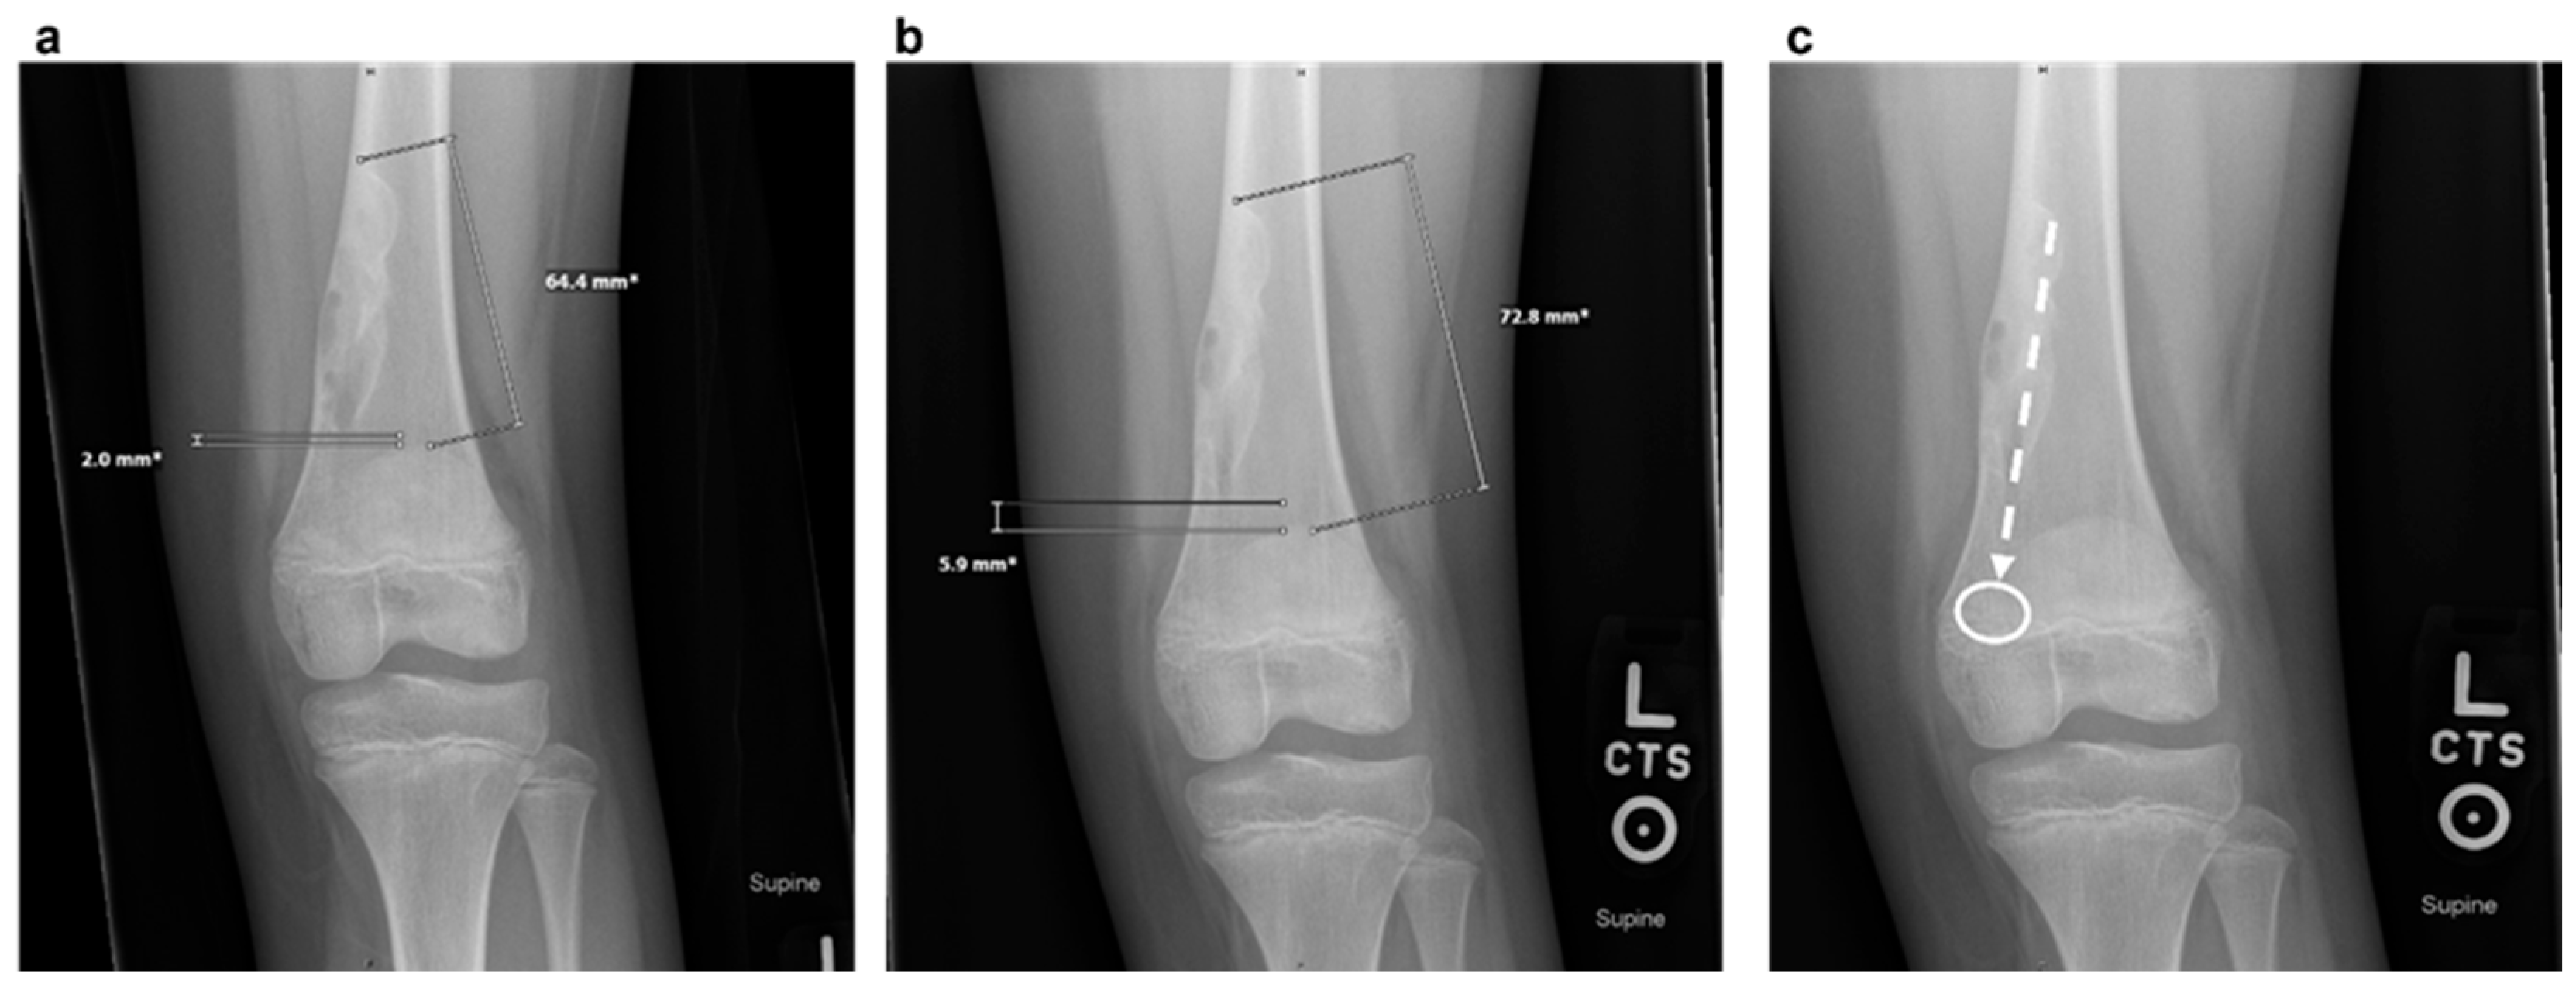

Plain radiographs typically show a well-demarcated, lytic lesion located eccentrically within the metaphysis of the affected bone. Over time, as the child grows, NOFs tend to migrate away from the growth plate towards the diaphysis due to bone remodeling [6]. Unlike enchondromas, which often present centrally within the medullary cavity and exhibit a chondroid matrix, NOFs are uniquely characterized by their eccentric location, elongated shape fibrous matrix and sclerotic border. This differentiation underscores the diagnostic importance of radiographic positioning and lesion morphology. As the defect migrates away from the tendon insertion, an imaginary line can often be drawn along the lesion’s long axis, pointing toward the soft tissue insertion from which the defect presumably arises. This is illustrated in Figure 1.

Figure 1. Images (a) and (b) demonstrate migration of the non-ossifying fibroma in a 9-year-old girl over a 6-month time span. Image (c) demonstrates the major axis of the non-ossifying fibroma with an imaginary line (dashed arrow) pointing toward the gastrocnemius insertion (white circle) as is a typical migration pattern for non-ossifying fibromas.